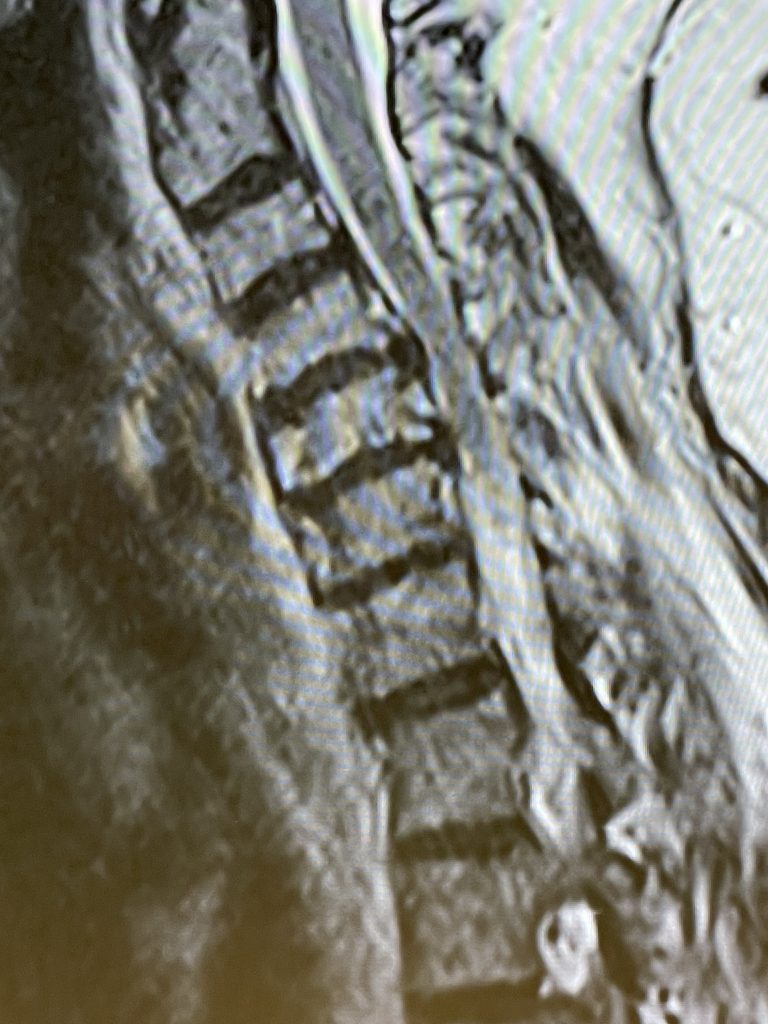

Figure 1: Sagittal T2-weighted MRI demonstrating a kyphotic cervical spine with C4-6 disc collapse with anterior osteophytes causing cord compression

Here is the case of a 51 year-old female who had a ten year history of severe neck pain with severe right arm pain, numbness, and weakness. She weighed over 300 pounds. She had failed all means of conservative management including medicines, physical therapy, chiropractic care, and epidurals. MRI demonstrated a reverse of the normal curvature of the cervical spine with large disc osteophyte complexes compressing the spinal cord (Fig 1). The C4-5 disc osteophyte was larger causing severe anterior compression of the spinal cord, worse on the right side (Fig 2). This correlated with the patient’s clinical findings. Therefore surgery was recommended. Patient underwent an anterior cervical discectomy and fusion with a plate from C4-C6. We were able to get her into a good position. Although there was a very deep exposure through the fat layer, it was not too bad to expose the face of the spine (Fig 3). Because there is less muscle, tissue planes open up actually easier sometimes particularly in women because of a relative decrease in muscle mass. The same goes for exposure of the lumbar spine. The majority of “herniated discs” in the cervical spine are actually bony protrusions we call osteophytes. After you clear away all the other cartilage that is the soft part of the disc, the way to get rid of that C4-5 osteophyte which acts like a sheet of bone at the posterior aspect of the disc space, is to drill it down to a fine shell and remove it with a special tool. This tool is called a Kerrison and has a very thin footplate that allows a plane between the osteophyte and dura which is being compressed and bites away this bone. The patient had good relief of her symptoms postoperatively.